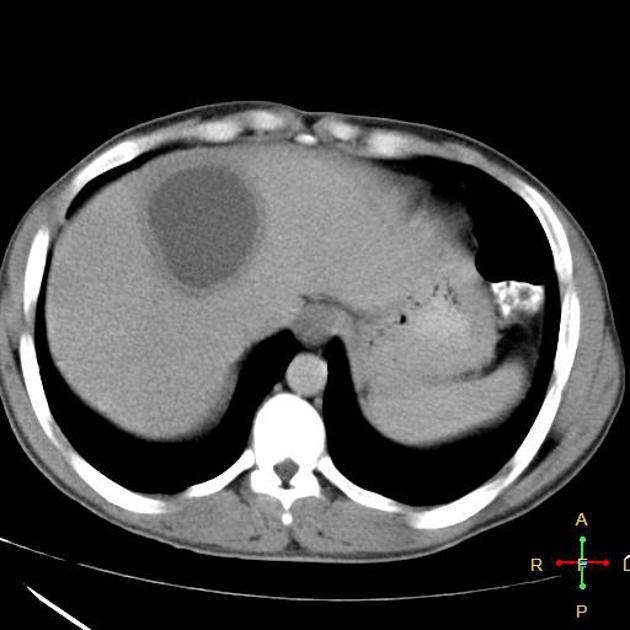

26 yo Mexican M w/ RUQ pain and low fevers

(a) Dx = amebic abscess by intestinal protozoan, entamoeba histolytica

- abdominal pain, fever, leukocytosis, liver abscess of imaging

(b) Tx = empiric metronidazole